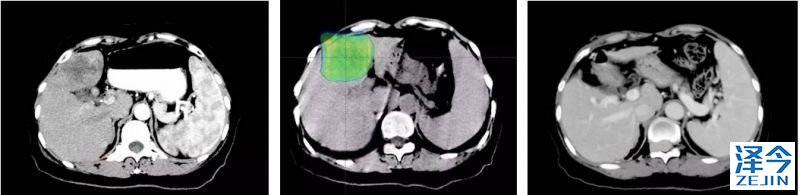

左:质子治疗前检查图像:肝右叶前段见类圆形低密度影,呈不均匀强化,边界清楚

中:质子治疗剂量分布:剂量分布均匀,包绕肿瘤组织,对周围正常肝组织保护好

右:质子治疗九年后复查图像:肝右叶肿瘤消失